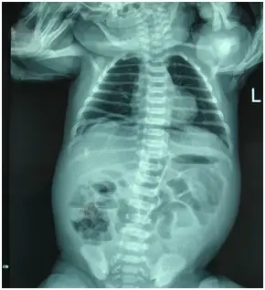

X光拍片检查:通常医生会给孩子做腹部立位片检查,发病后4~6小时可见多部位、多排肠管胀气,同时可出现多个腹部气液平。这是肠梗阻的重要诊断依据之一。